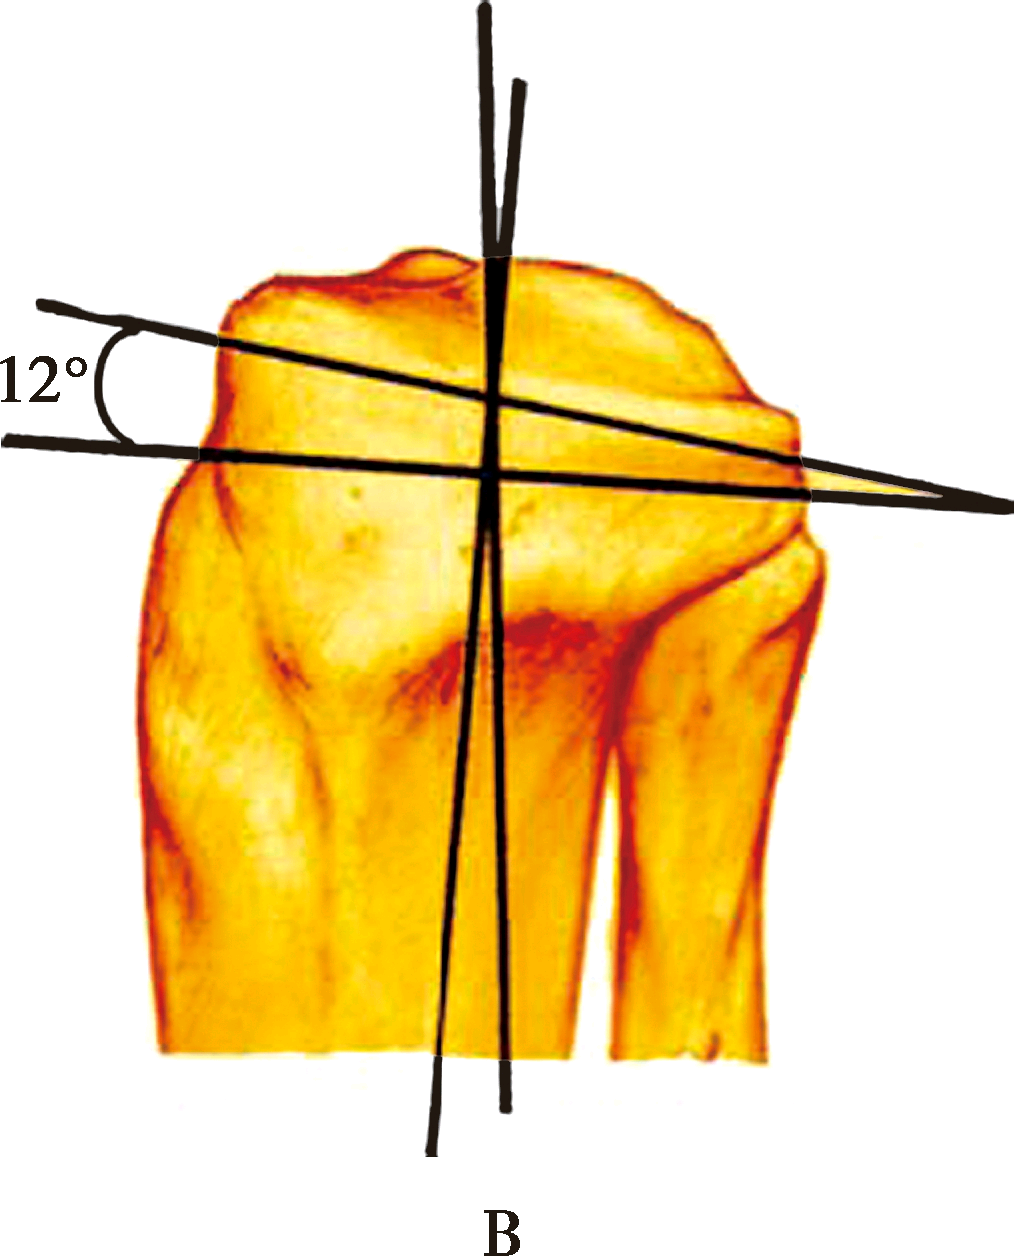

股骨后髁外旋3°截骨,以获得矩形的屈曲间隙

正常胫骨平台有3°~5°内倾,现代膝关节假体设计通常将胫骨假体与胫骨解剖轴垂直,从而忽略了解剖上存在的内翻。这样当膝关节屈曲时,要求股骨假体也相应外旋3°~5°安放,即多切除一些股骨内髁后方的骨质,以保证获得矩形的屈曲间隙和内外侧韧带张力相等。如果股骨后髁内外侧对称切骨,屈曲间隙将成为梯形,假体植入后,屈膝位外侧副韧带较为松弛,引起关节外侧不稳定。另外,适当外旋股骨假体,可使髌骨滑车沟向前外侧旋转,减少Q角及髌骨向外脱位的倾向。

股骨旋转轴线

PC线为股骨后髁连线

EP线为股骨内外上髁连线

Whiteside线为股骨滑车切迹的最低点与股骨髁间窝中点的连线

1.骨旋转轴线

临床还可根据股骨后髁连线(posterior condylar line,PC线),股骨髁前后轴线(Whiteside线)和股骨内外上髁连线(epicondylar line,EP线)确定股骨假体安放的外旋角度。

2.PC线

最常用的参照,如果后髁的正常解剖结构遭到破坏,如膝外翻外髁磨损变小,股骨后髁连线本身也会异常内旋,如仍以此线为参照,会导致股骨假体内旋。

3.EP线

由于髌骨、韧带等软组织的阻挡,术中准确确定内外上髁最高点有一定困难,但在膝关节翻修手术中,由于股骨髁前后均有严重骨缺损,EP线可能成为唯一的参照。

4.Whiteside线

股骨髁前后轴线,即髌骨滑车最低点与股骨髁间窝中点的连线。股骨假体应与该线垂直。如果滑车发育不良或某些外翻病例,会影响股骨髁前后轴线的准确性。